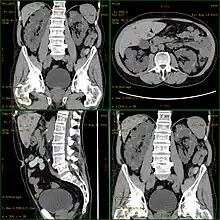

![]() | |

| Severely affected polycystic kidneys removed at time of transplantation | |

| Diagnostic method | MRI, CT scan, Ultrasound[1] |

Diagnosis may be suspected from one, some, or all of the following: new onset flank pain or red urine; a positive family history; palpation of enlarged kidneys on physical exam; an incidental finding on abdominal sonogram; or an incidental finding of abnormal kidney function on routine lab work (BUN, serum creatinine, or eGFR). Definitive diagnosis is made by abdominal CT exam.

Polycystic kidney disease can be ascertained via a CT scan of abdomen, as well as an MRI and ultrasound of the same area.[23] A physical exam/test can reveal enlarged liver, heart murmurs and elevated blood pressure.[1]